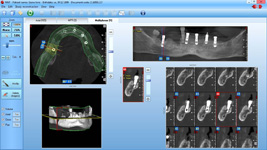

Pro následné plánování využíváme počítačové programy NewTom Implant Planning a coDiagnostiX, které slouží na plánování vhodných pozic pro zavedení implantátů, operačních šablon, kostních bloků, pozdějších protetických náhrad, ...

Lékař si vytvoří všechny typy zobrazení potřebných pro naplánování – tedy 2D snímky (panoramatický), příčné řezy i 3D model.

Vidí zde i důležité anatomické útvary – čelistní dutinu, průběh nervu atd. Po proměření množství kosti – šířky i výšky vybere z databáze vhodný typ implantátu a umístí ho do požadované lokality.

Ihned vidí jeho pozici ve všech 3 rovinách a na všech snímcích i 3D modelu. Může upravovat podle potřeby jeho pozici, sklon atd.

Všechny vybrané a správně umístěné simulované implantáty se ukládají do „počítačové karty“ pacienta s jejich pozicí, délkou, průměrem, typem i sklonem.

Lékař i pacient tedy ještě před vlastní operací vidí, jak by mělo ošetření probíhat a vypadat.

coDiagnostiX – Dental Wings

Jedná se o externí plánovací program, spojený se zubní laboratoří a frézovacím centrem, který využívá dat získaných z 3D rentgenu čelisti, otisku zubů a dásně (scanu zubů a dásně) a finálního návrhu protetické náhrady.

Tento program umožňuje tříprostorovou počítačovou simulaci při plánování pozic implantátů. Součástí programu je i databáze, ve které mohou být uloženy všechny typy implantátů od všech výrobců, včetně jejich délek, průměrů i tvarů.

Vidí zde i důležité anatomické útvary – čelistní dutinu, průběh nervu atd. Po proměření množství kosti – šířky i výšky vybere z databáze vhodný typ implantátu a umístí ho do požadované lokality. Ihned vidí jeho pozici ve všech 3 rovinách a na

všech snímcích i 3D modelu. Může upravovat podle potřeby jeho pozici, sklon atd.

Všechny vybrané a správně umístěné simulované implantáty se ukládají do „počítačové karty“ pacienta s jejich pozicí, délkou, průměrem, typem i sklonem. V programu také lékař navrhuje chirurgické šablony pro řízenou nebo navigovanou implantaci.